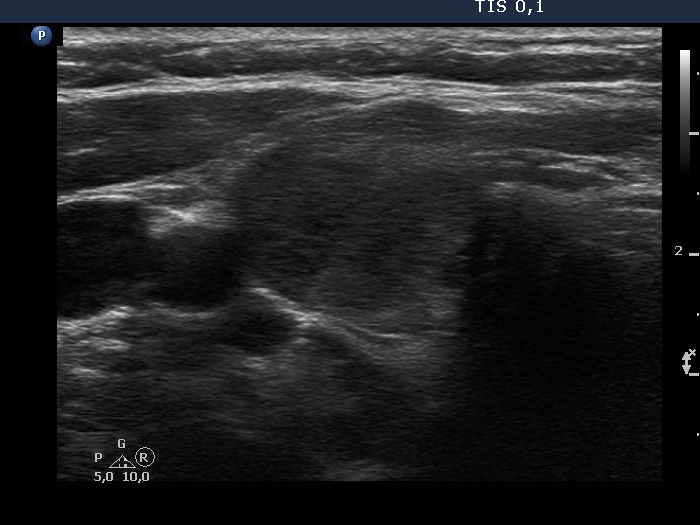

Second examination 3 years later (second, fourth and sixth rows of images):

Ultrasonography. Compared with the previous examination, both the number and the size of discrete lesions in the thyroid have increased.